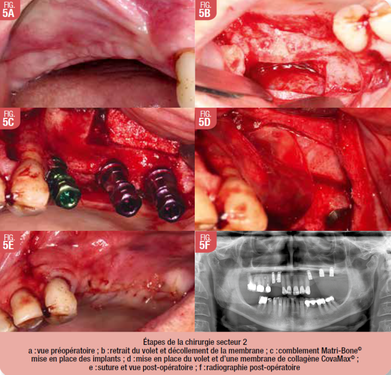

Préparation secteur 2

Les étapes pour l’aménagement osseux et la pose des implants en secteur 2 étaient (Fig. 5), anesthésie locale avec articaïne adrénalinée à 1/100000eme, désinfection endo et exo-buccale à la bétadine et champage stérile, incision sur crète avec décharge mésiale, lambeau de pleine épaisseur, aménagement sinusien par accès latéral à la piezo-chirurgie et forage des sites pour 3 implants (Fig. 6, b), mise en place du matériau de substitution osseuse (Matri-Bone®), pose des implants TSV Zimmer® torque à 35N avec vis de couverture pour 24 26 et 27, fermeture du site avec remise en place du volet osseux et membrane collagénique (CovaMax®), fermeture hermétique du site avec suture en monocryl 5.0. (Fig. 6), hémostase et conseils post-opératoires.

Les implants présentaient une bonne stabilité primaire à la fin de l’intervention. Le saignement lors de l’intervention était normal. La patiente est revue à 15j post-opératoire pour contrôle et la dépose des points. La cicatrisation est normale.